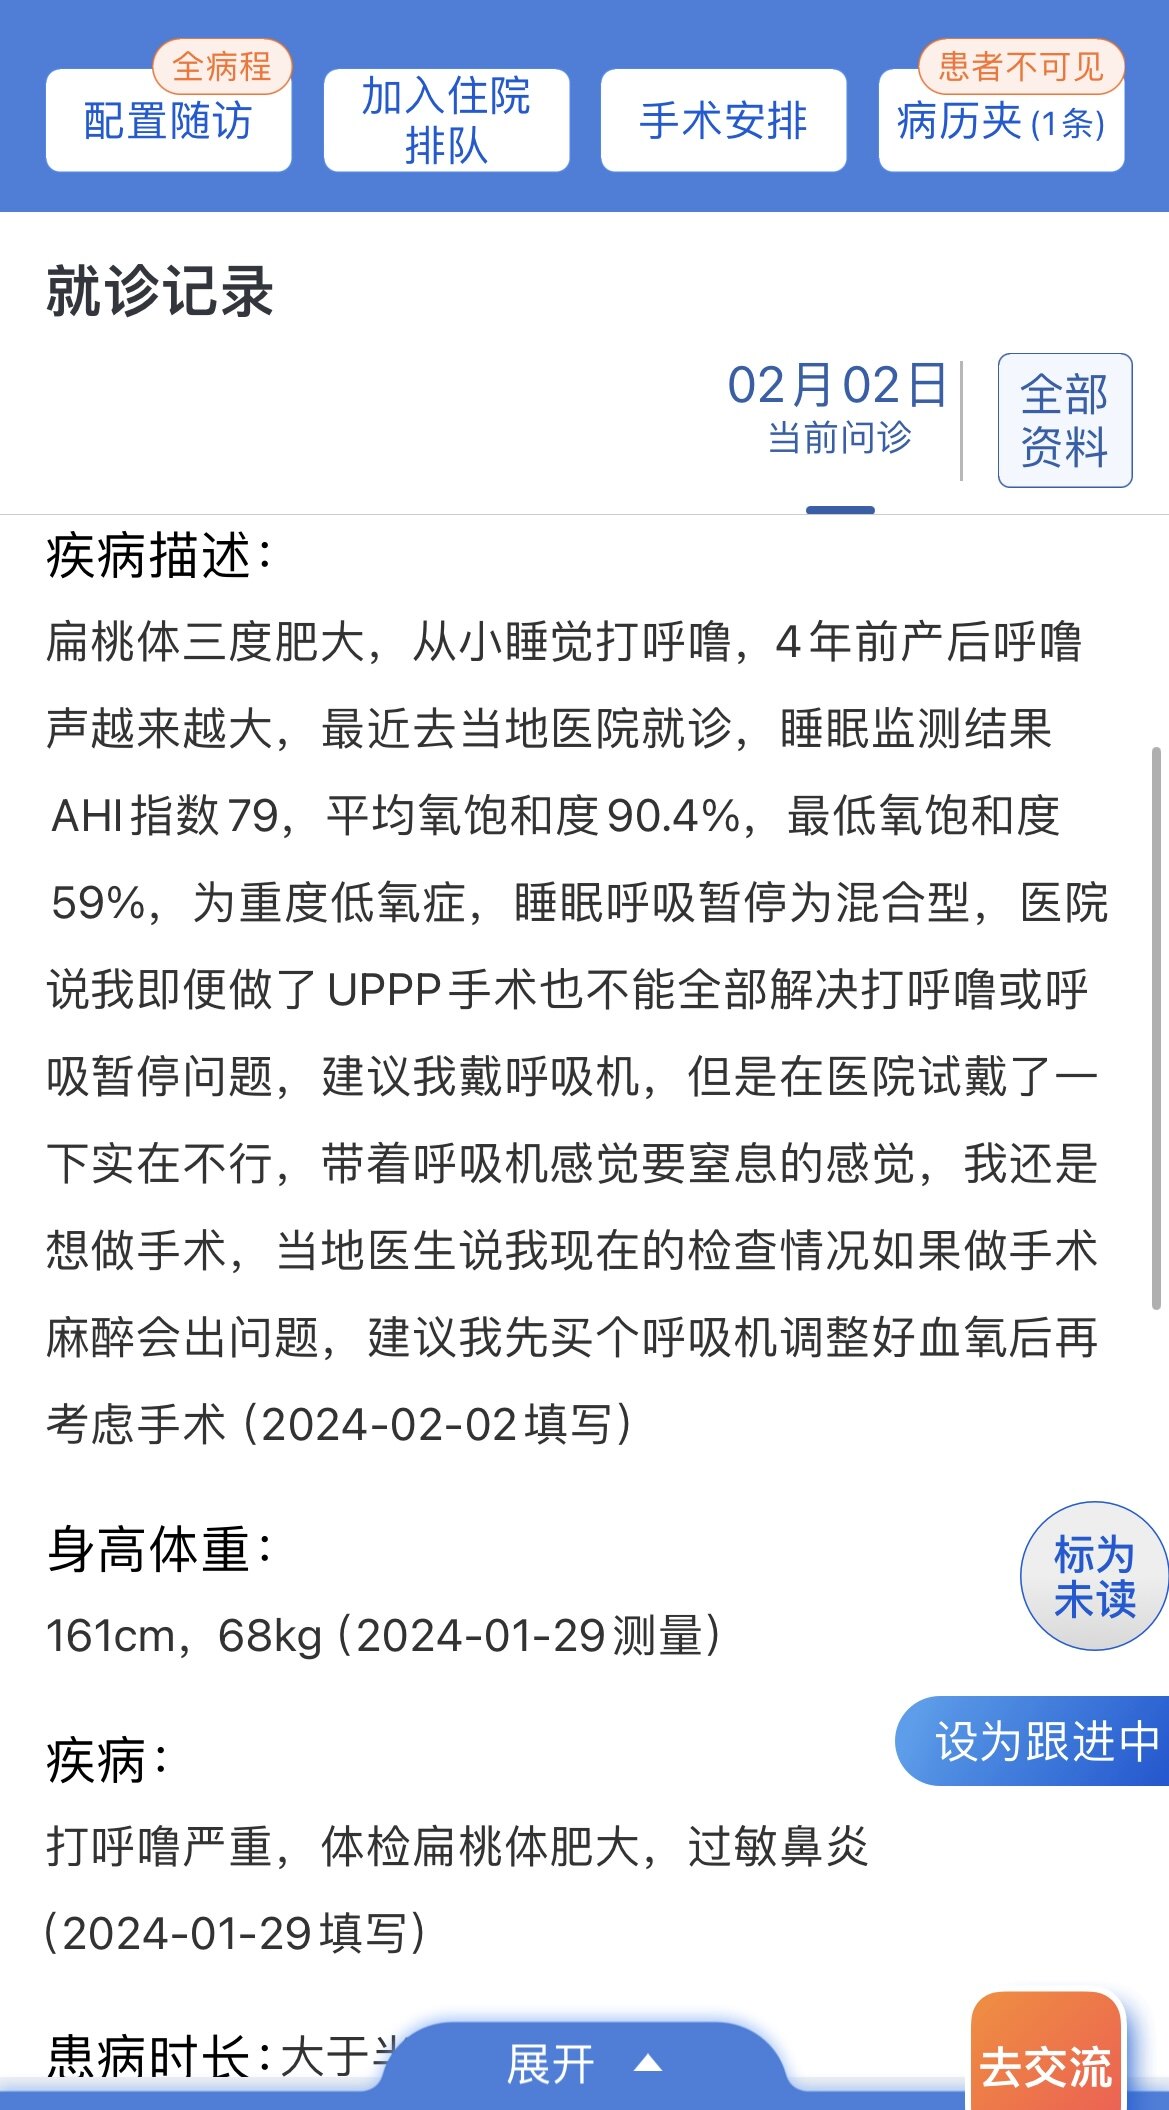

之前同一天做过“鼾症兄弟”、“鼾症兄妹”和“鼾症父女”,这是第一次给“鼾症母女”同一天手术。这对母女来自新疆巴音郭楞,重度鼾症父亲37岁,因为扁桃体肥大,自小打鼾,4年前产后打鼾加重,伴夜间憋醒,严重影响睡眠,当地医生建议患者戴呼吸机,但是她无法耐受呼吸机。电话咨询后,下定决心来广州找我手术。同时她也把4岁女儿打鼾和张口呼吸的情况也详细告诉我,鼾症女儿因为扁桃体3度肥大,腺样体堵塞后鼻孔2/3,造成张口呼吸,对于这样的孩子,一定需要早点手术干预,不然会影响面部发育和生长发育,甚至智力发育。所以我就让她们母女一起来广州找我手术。手术时发现母女俩的扁桃体肥大,因为女孩子4岁,我常规保留双下极扁桃体的1/5和腺样体的1/5。希望母女手术后身体早日恢复正常!有一个安稳的睡眠质量,健健康康的生活!